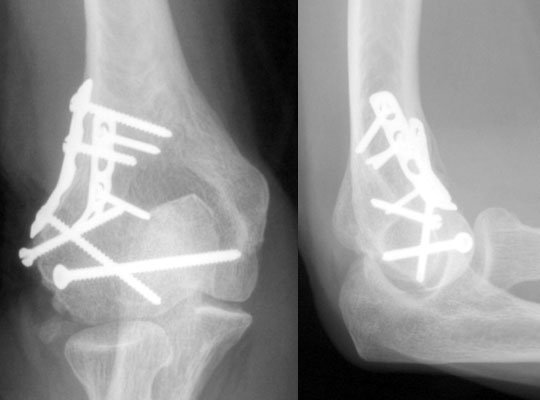

تثبيت الكسور بالشرائح والمسامير

ومع تقدم العلم اختلفت أنواع تثبيت الكسور جراحيًا تبعًا لنوع الكسر ومكانه ، وأيضًا تبعًا لعمر المريض وضمن هذه الأنواع هي تركيب الشرائح والمسامير الطبية، وتركيب المثبتات الخارجية والمسامير النخاعية ويحتاج الطبيب المعالج لعمل بعض الأشعات اللازمة لتحديد النوع المناسب لتثبيت الكسور.

ويقوم الطبيب بتثبيت الكسور والشروخ في جسم الإنسان بواسطة تركيب شرائح طبية ومسامير تساعد على التئام الكسر بشكل طبيعي وفي مكانه الصحيح مما يضمن للمريض استعادة حياته اليومية بشكل سريع وبدون ألم. وتناسب هذه الشرائح والمسامير بصفة خاصة الكسور القريبة من المفاصل.

ويتقبل جسم الإنسان هذه الشرائح والمسامير بشكل عادي فلا يعتبرها جسم غريب عنه أو يرفضها، وذلك لأن هذه الشرائح مصنوعة من عدة سبائك وهي: سبائك التيتانيوم وسبائك النيكل والكروم الممزوجة بالحديد وأيضًا سبائك الكوبالت.